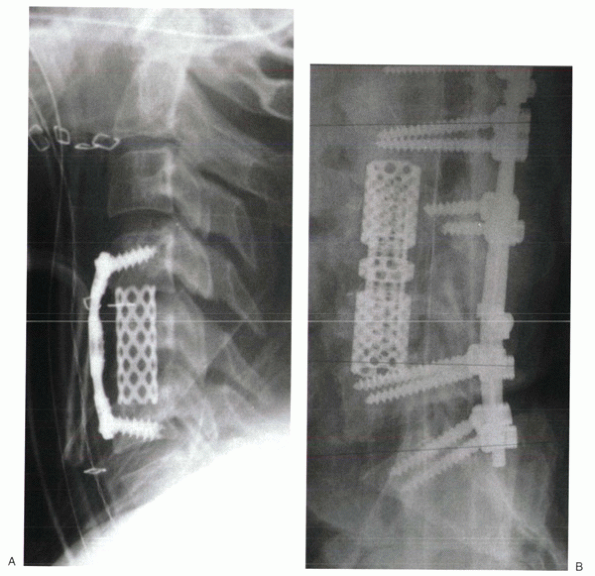

Figure 28-1 (A) Granulomatous infection led to a progressive kyphotic gibbus, intractable pain, and neurologic compromise. (B)

Anterior corpectomy of T12 and L1 was followed by allograft strut interposition to reconstruct the anterior column. Posterior instrumented fusion was performed in a second stage. |

Anterior column reconstruction is necessary when the anterior aspects

of the spine (vertebral body or intervertebral discs or both) are

missing or incompetent. The vertebral bodies can be eroded or destroyed

by infection or tumor (Fig. 28-1A). Highly comminuted burst fractures can result in anterior column insufficiency.

Removal of the vertebral body during surgery necessitates anterior column reconstruction.

![]() |

|

Figure 28-2

Titanium mesh cages can be filled with morcellized, cancellous autograft. They can be used to reconstruct the anterior column after cervical (A), thoracic, or lumbar (B) corpectomy. |